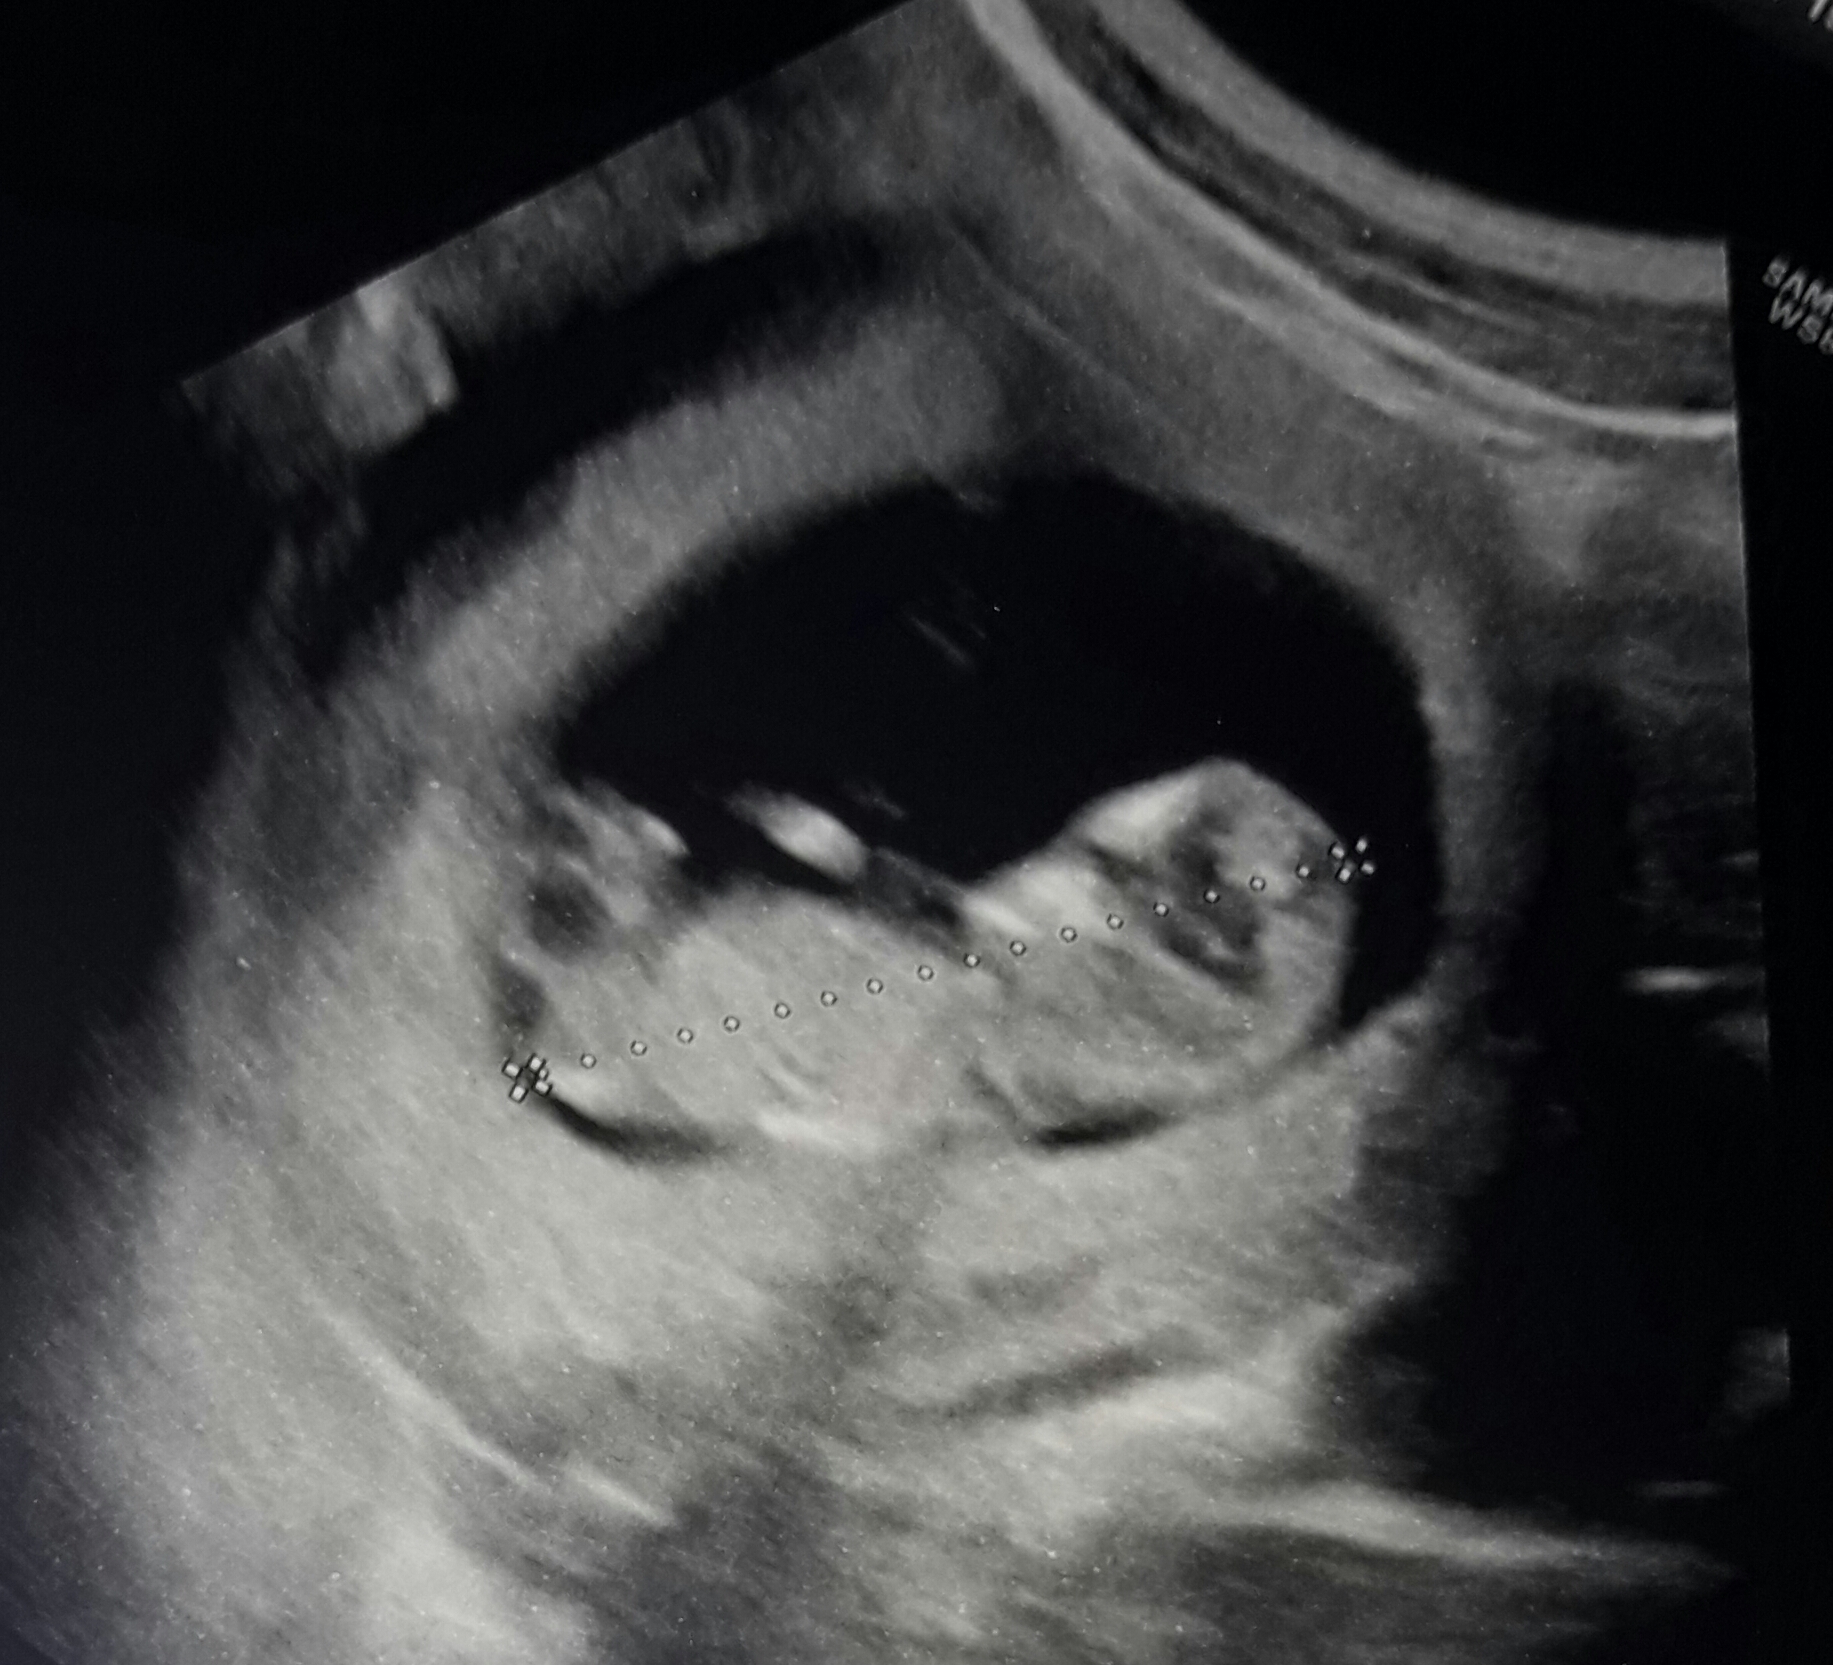

What is it? I m 12 weeks Attachment 35288

What gestational age? Your first image looks girly to me, but if this is the earlier end of 12 weeks it's too soon to really guess. Closer to 13 is better.

The baby is exactly 11+5 Week gestation.. the Next scan it Will at 16 Week.. the ginecologist tell me sure if Will be a boy or girl.. I would like to know before :pregnant: sorry flr my english but i m Italian

11+5 is too early to guess accurately. Nub shots are more accurate around 13 weeks.